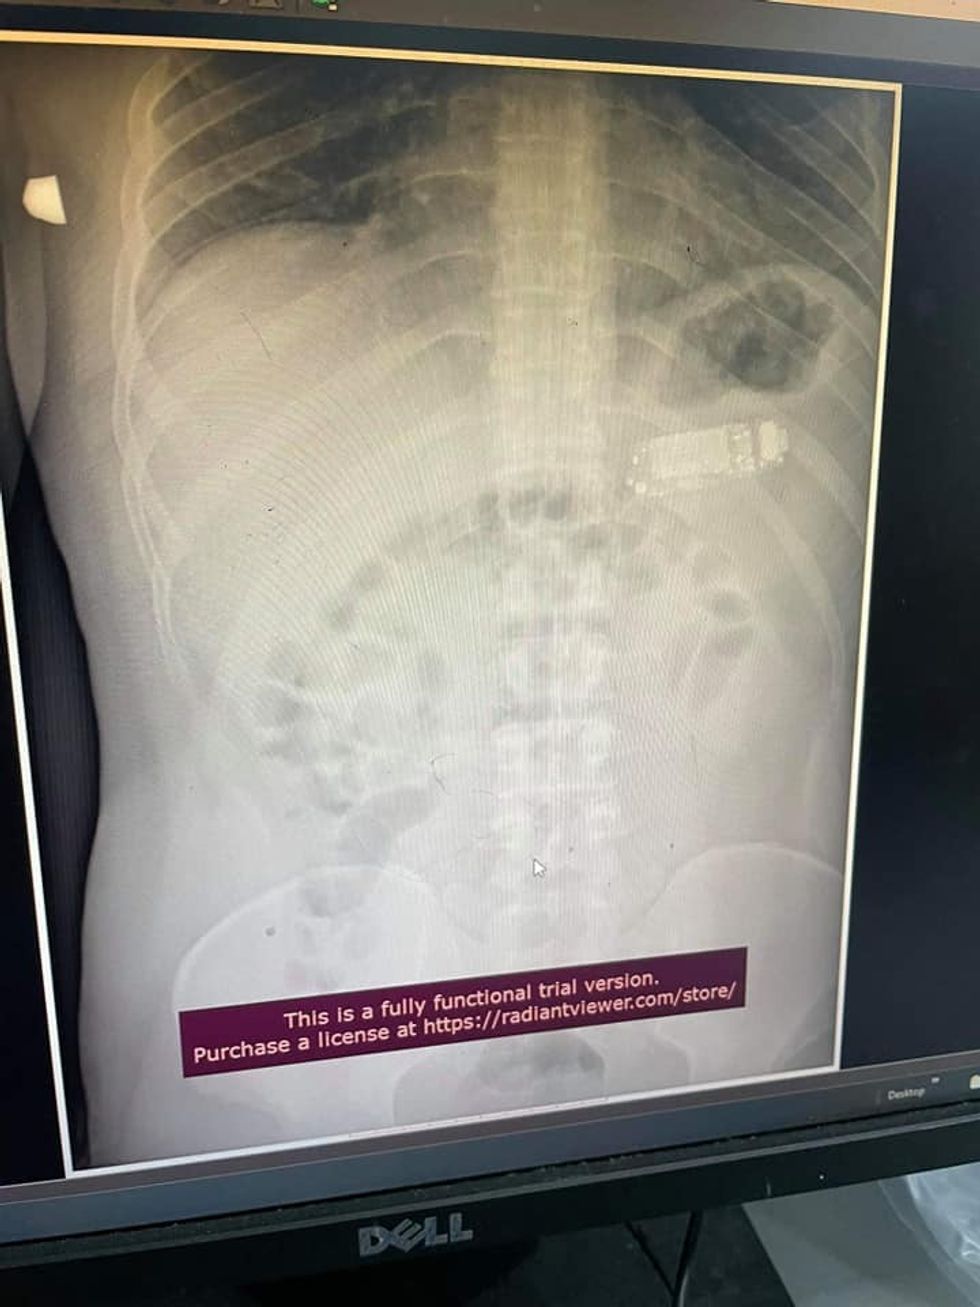

Në Klinikën e Urologjisë të Qendrës Klinike Universitare të Kosovës, mjekët, bashkë me ekipin e anesteziologëve, kryen një intervenim kirurgjik te një pacient, të cilit i hoqën më shumë se 20 gurë në veshkë dhe në kanalin urinar.

Në njoftim thuhet se pacienti me inicialet S.M., i moshës 52 vjeçare, kishte dhimbje në regjionin lumbal të anës së majtë për një kohë të gjatë.